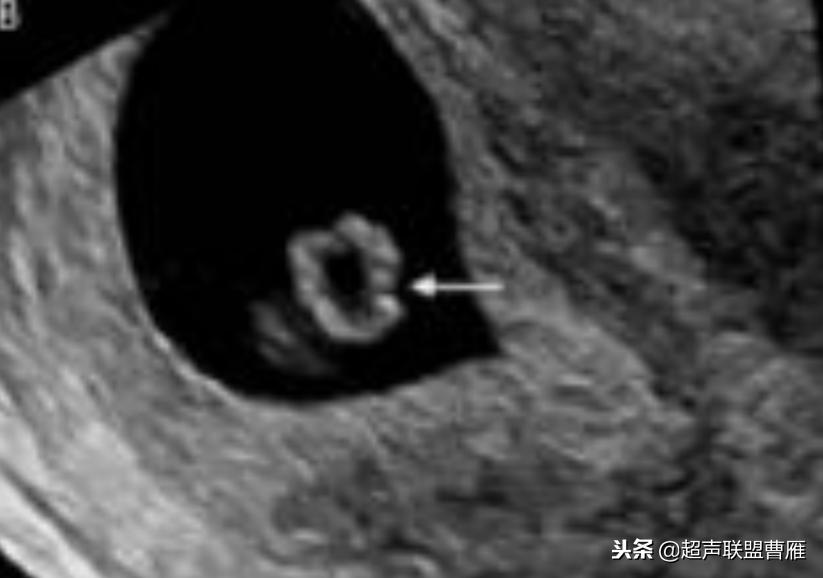

卵黄囊不规则内有回声

· 卵黄囊内有回声:临床意义不确定

卵黄囊回声增强,预后不良